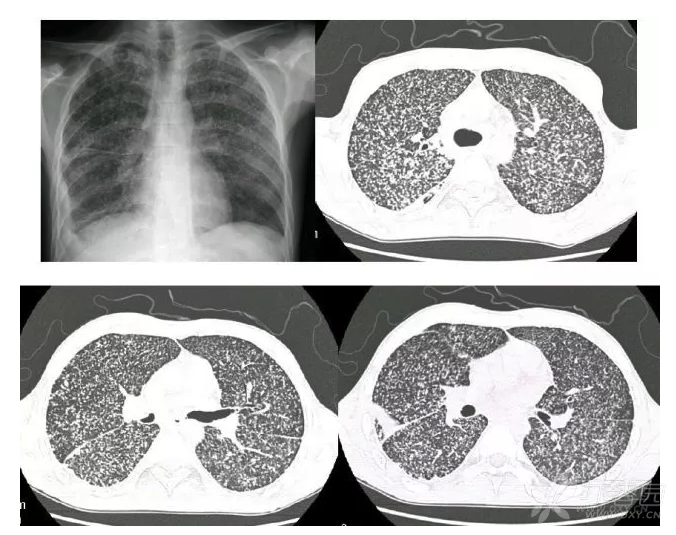

【影像读片】诊断周围型肺癌4年后的ct片 [病例帖]

周围型肺癌:病灶最大径>30 mm,右肺上叶后段可见一肿块,边缘分叶.